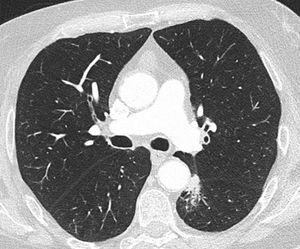

As an example, we show here a real-life adenocarcinoma case (pT1bN0M0) from Clinica Universidad de Navarra. This patient presented a pulmonary nodule in the left lower lobe, located in a challenging paraaortic region, accompanied by perilesional atelectasis (Fig. 4). EarlyCDT lung test was performed to assess nodule malignancy. Out of the seven lung cancer-associated autoantibodies tested, p53 and NY-ESO-1 showed elevated levels indicating a positive result for nodule malignancy (“Moderate Level [M]” according to the test scale).